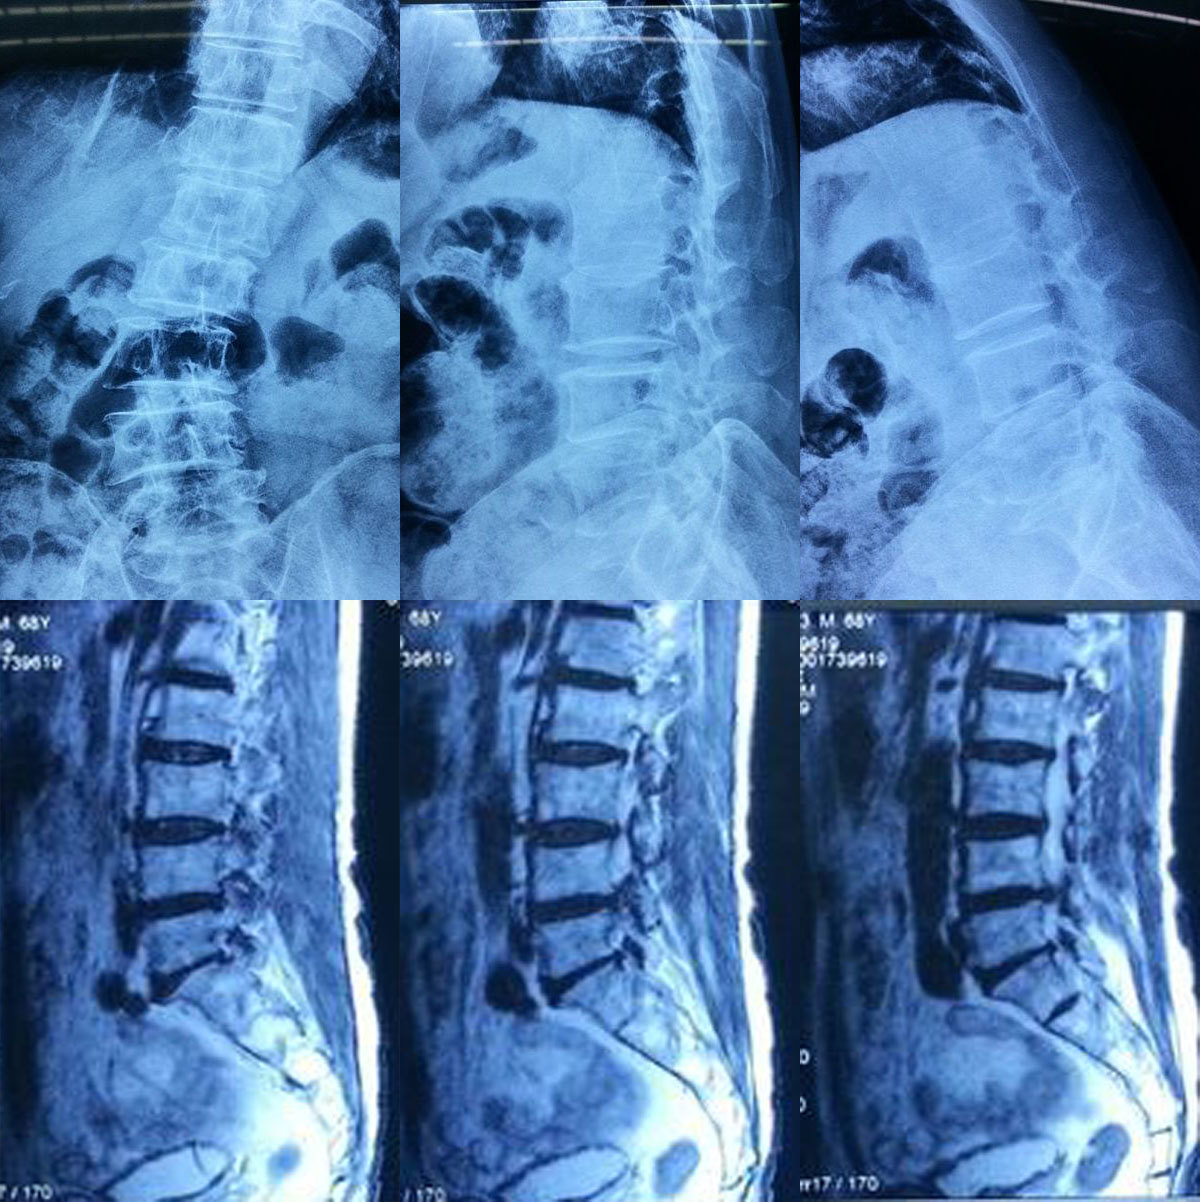

先天腰间盘突出,脊柱达到45度弯曲的人有多痛苦?

图片尺寸1536x2048